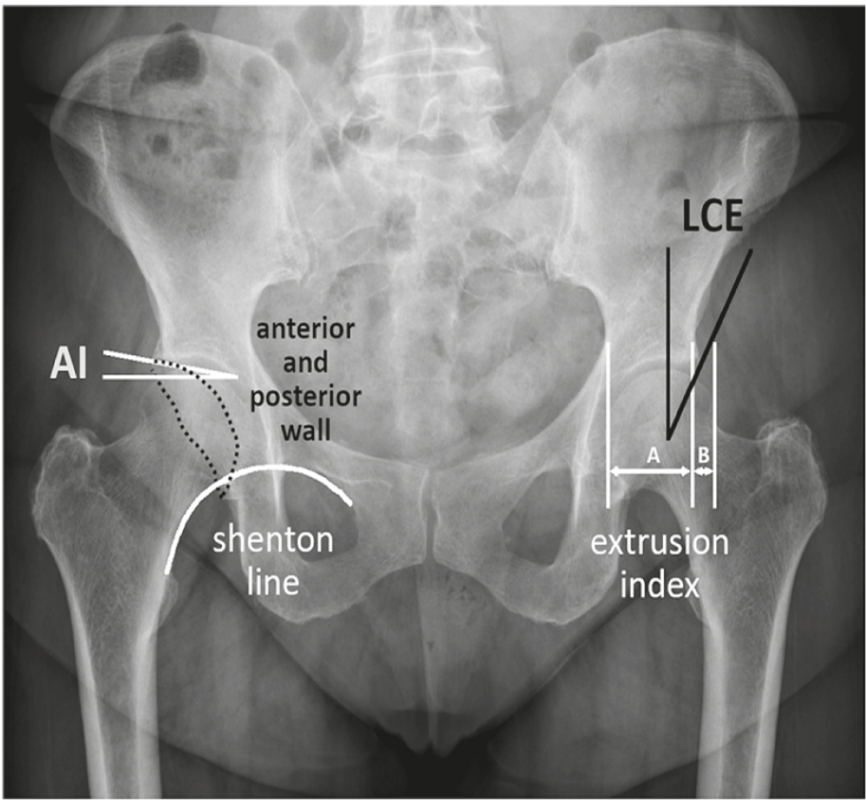

Analysis of orthopaedic X-rays relies on a set of angles and ratios that can be directly measured on the radiographs (Fig. 1) [1][2]. However, recent trends in the automatization and computerisation of health diagnostics introduced an intermediate step where radiographs are used to identify coordinates of anatomical landmarks (i.e. anatomically meaningful points on images). Relevant angles and ratios are then calculated from the landmark locations [3][4]. Unfortunately, the available commercial software is limited in what data it can produce at a large scale. Simultaneously, time constrains doctors regarding what data they can collect manually. To continue producing relevant research, they need a flexible and scalable approach that can be re-used with any new set of measurements in emerging projects.

Refer to caption

Figure 1: Schematic illustration of radiographic hip parameters on an AP pelvic radiograph: AI – acetabular index, LCE – lateral central edge; A – covered femoral head; B – undercovered femoral head. (Reproduced from Fig.4 by Mitterer et al. (2022)).